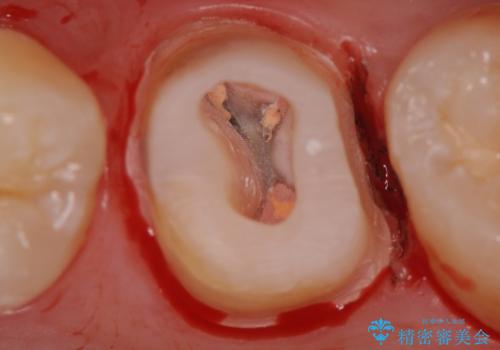

被せ物を除去し、根管治療を進めた後に新しい被せ物を装着していきます。

- 左上6:仮歯+ジルコニアクラウン/11,000円+121,000円 , 再根管治療(リトリートメント)+土台(ファイバーコア)/143,000円+22,000円費用は治療当時の料金となります

本来は歯茎をしっかりと下げる外科処置が適応となるケースでしたが、ご希望がなかったため最小限の侵襲に抑えて治療を行いました。

根の中を洗浄し、結果的に適合の良い被せ物をセットすることができました。